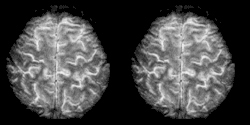

Cognitive neuroscience aims to reduce cognition to its neural basis using new technologies such as fMRI, repetitive transcranial magnetic stimulation (rTMS) and Magnetoencephalography (MEG) as well as older methods such as Positron emission tomography (PET) and Electroencephalography (EEG) studies. Due to the correlational designs used in fMRI, many scientists have coined this up and coming field as the new phrenology in the sense that techniques such as fMRI rely heavily on complex statistics.[17] Type 1 errors can lead scientists to draw premature and incorrect causal relationships if improper designs are used.[18]